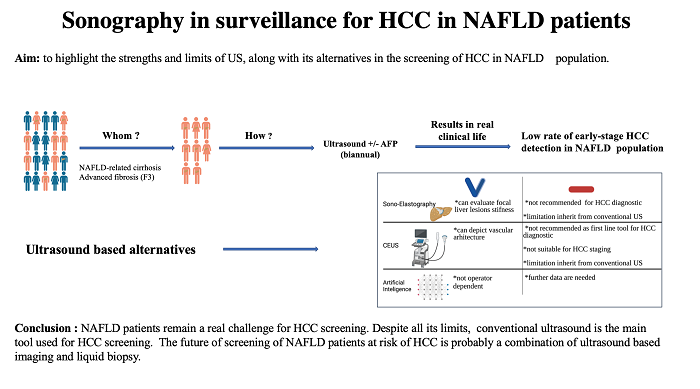

Figure 1. Liver haemangioma in a 40-year-old woman examined in the supine position. Conventional US revealed a hypoechoic lesion in segment VII and a liver parenchyma with an increased echogenicity (A). One year later, after the patient lost 10 kg, the known hypoechoic lesion described in segment VII had a hyperechoic appearance, typical for haemangiomas. The adjacent liver parenchyma had a significantly decreased echogenicity compared with the previous examination (B). Courtesy Dr. Delgado Gabriela, Department of Visceral Surgery and Medicine, Inselspital, Bern University Hospital, University of Bern, Bern 3008, Switzerland.